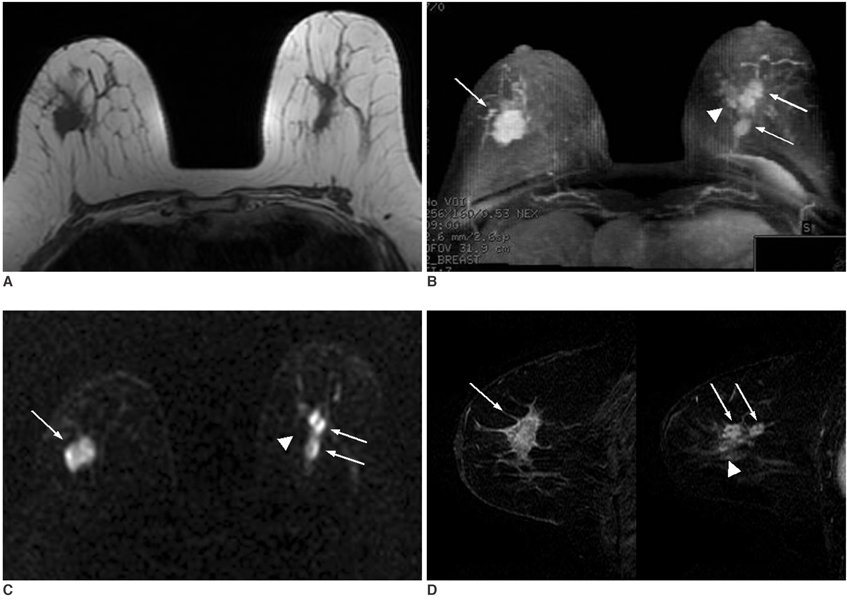

We wanted to evaluate the role of diffusion-weighted imaging (DWI) and the apparent diffusion coefficient (ADC) for detecting breast tumors, as compared with the T1- and T2-weighted images. MATERIALS AND METHODS: Forty-one female patients underwent breast MRI, and this included the T1-, T2-, DWI and dynamic contrast-enhanced images. Sixty-five enhancing lesions were detected on the dynamic contrast-enhanced images and we used this as a reference image for detecting tumor. Fifty-six breast lesions were detected on DWI and the histological diagnoses were as follows: 43 invasive ductal carcinomas, one mucinous carcinoma, one mixed infiltrative and mucinous carcinoma, seven ductal carcinomas in situ (DCIS), and four benign tumors. First, we compared the detectability of breast lesions on DWI with that of the T1- and T2-weighted images. We then compared the ADCs of the malignant and benign breast lesions to the ADCs of the normal fibroglandular tissue. RESULTS: Fifty-six lesions were detected via DWI (detectability of 86.2%). The detectabilities of breast lesions on the T1- and T2-weighted imaging were 61.5% (40/65) and 75.4% (49/65), respectively. The mean ADCs of the invasive ductal carcinoma (0.89 +/- 0.18x10(-3)mm2/second) and DCIS (1.17 +/- 0.18x10(-3)mm2/ second) are significantly lower than those of the benign lesions (1.41 +/- 0.56x10(-3)mm2/second) and the normal fibroglandular tissue (1.51 +/- 0.29x10(-3)mm2/ second). CONCLUSION: DWI has a high sensitivity for detecting breast tumors, and especially for detecting malignant breast tumors. DWI was an effective imaging technique for detecting breast lesions, as compared to using the T1- and T2-weighted images.

Figure